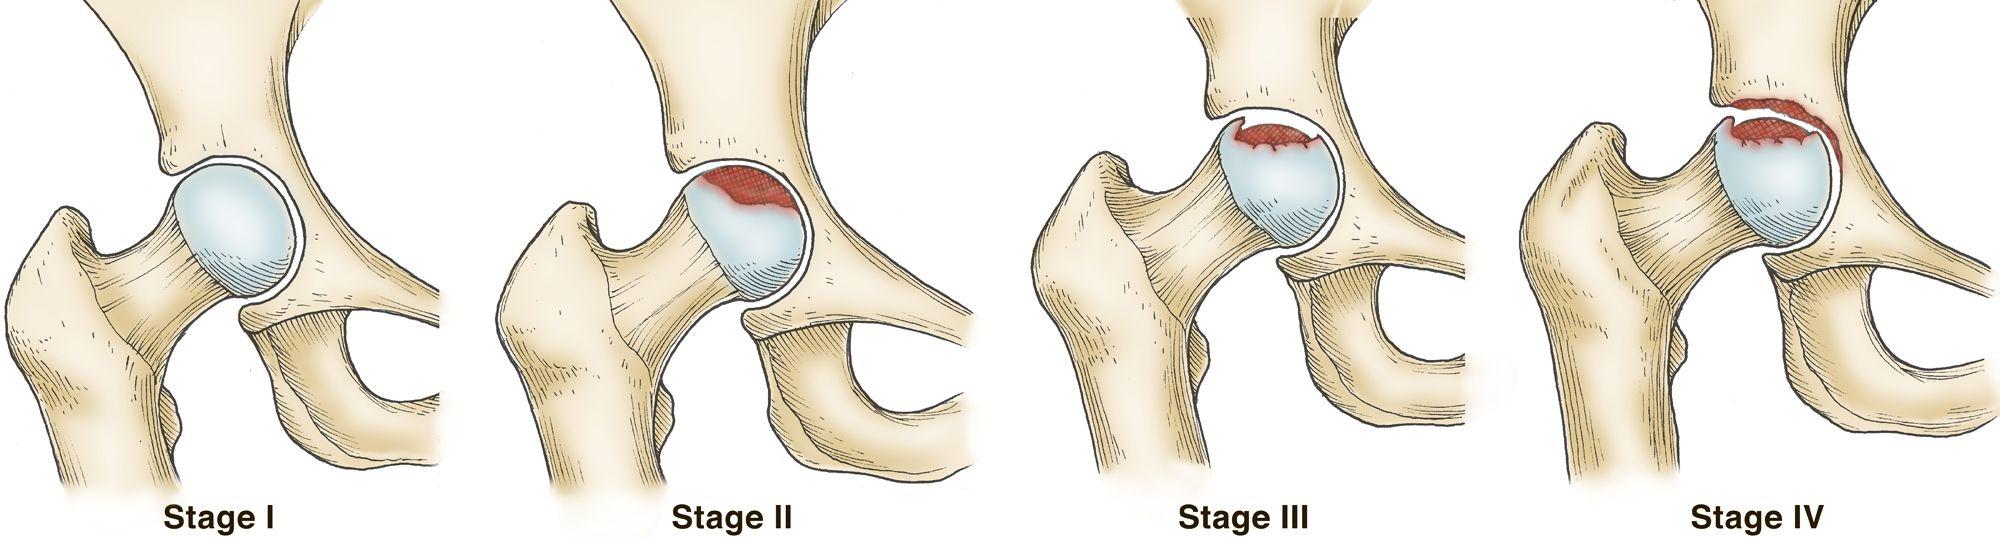

骨坏死的四个阶段。该疾病可以从正常、健康的髋关节(I 期)发展为股骨头塌陷和严重的骨关节炎(IV 期)。

转载并改编自 Beaule PE, Amstutz, HC:髋关节 III 期和 IV 期骨坏死的管理。J Amer Acad Orthop Surg 2004;12:96-105。